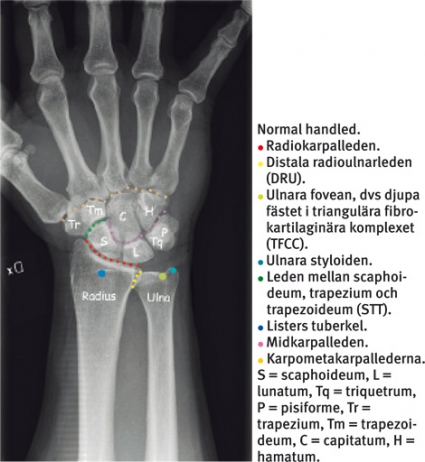

Handleden består av distala radius och ulna, distala radioulnarleden, radiokarpalleden, carpus med proximala karpalbensraden (scaphoideum, lunatum, triquetrum och sesambenet pisiforme), den rörliga midkarpalleden, den distala karpalbensraden (trapezium, trapezoideum, capitatum, hamatum) och traditionellt även karpometakarpallederna (CMC).

Carpus tillhör kroppens mest komplicerade ledsystem, och denna artikulation kan ställa in handen i exakt finmotoriskt läge samtidigt som en tiofaldig kraftöverföring kan ske från fingertopparna till mellanhanden. 80 procent av denna kraft överförs vidare mellan carpus och radius. I normalfallet överförs resterande 20 procent mellan carpus och ulna.

Radius roterar runt ulna, som ligger still. Ulna är viktig för stabilitet och rörelse men är inte utformad för att ta upp axiala krafter. Distala radioulnarleden är däremot direkt kraftbärande vid lyft med flekterad armbåge och neutralt roterad underarm. Inga senor fäster i proximala karpalbensraden, och här bidrar inte musklerna med någon dynamisk stabilitet. Stabiliteten beror i stället helt på den speciella benanatomin och de starka ligamenten mellan scaphoideum, lunatum och triquetrum.

Mellan benen i distala karpalbensraden, där handledens extensor- och flexorsenor fäster, finns ingen inneboende spänning eller någon nämnvärd rörlighet. Dessa ben rör sig mer som en gemensam enhet. Flexion/extension i handleden tas till 60 procent ut i radiokarpalleden. Resterande 40 procent av rörelseuttaget äger rum i midkarpalleden, dvs mellan proximala och distala karpalbensraden [7].

Scaphoideum är det enda ben som överbryggar de två karpalbensraderna. Scaphoideum fungerar därigenom som en länk mellan dem, vilket ger en stabiliserande effekt. Utan intakt scaphoideum eller skafolunärt ligament skulle carpus vara instabil, särskilt då den utsätts för kompressionskrafter. En s k karpal kollaps skulle då lätt kunna uppkomma. Trots sin stabiliserande effekt är scaphoideum mycket rörlig: 45° i två plan. Vid radialdeviation av handleden sker exempelvis en kraftig volarflexion av scaphoideum.

I carpus finns ett tjugotal väldefinierade ligament som bidrar till styrka och stabilitet. Dessa är uppdelade i extrinsic- och intrinsic-ligament. Extrinsic-ligamenten har sitt ursprung på radius eller ulna och fäster i carpus. Intrinsic-ligamenten har både ursprung och fäste inom carpus. Dessa är oftast tvärgående och djupt liggande ligament som förbinder två angränsande ben inom samma karpalbensrad.

Viktiga ligament i den proximala karpalbensraden är skafolunära ligamentet (mellan scaphoideum och lunatum) och lunotrikvetrala ligamentet, som förbinder lunatum med triquetrum. Den dorsala portionen av skafolunära ligamentet är starkast, medan den volara portionen av lunotrikvetrala ligamentet är starkast.